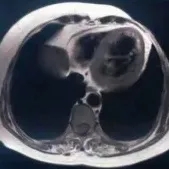

入院后监测患者病情变化,患者住院后经上述对症治疗,呼吸困难及胸闷症状逐渐好转。结合患者病史、既往及本次超声心动图改变,高度怀疑左室心肌致密化不全LVNC。为进一步明确诊断及评估心脏结构改变,完善了心脏磁共振检查。结果显示左室侧壁及心尖部过度肌小梁化,非致密心肌厚度大于致密心肌厚度的2~3倍,左心室整体收缩功能减弱,并见心尖部心内膜下钆延迟增强(图1)。

图1. 心脏磁共振